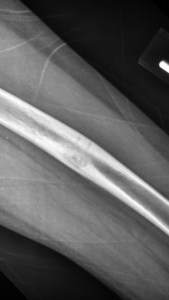

X-rays taken at 6 weeks post-surgery showed gradual healing of the bone.